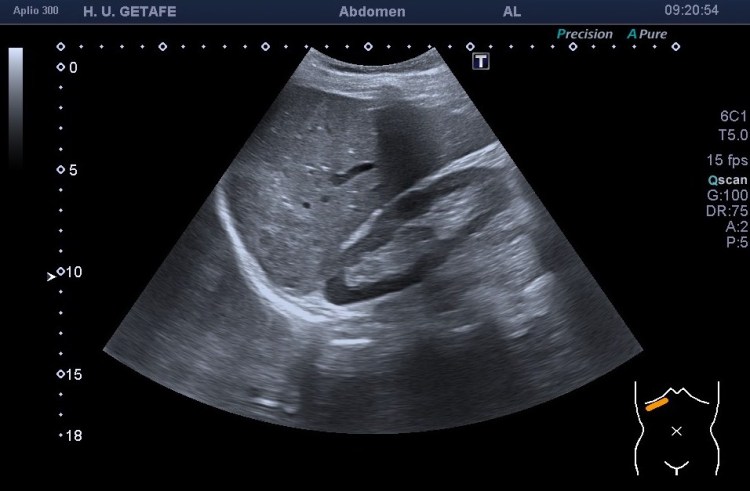

El caso en si mismo no tiene gran relevancia a no ser que la sospecha fuese que la masa que sabemos que es de un hemangioma atípico fuera de otra índole, pero ¿cómo podríamos sospechar que una LOE es maligna? Bien, hay varias maneras, hoy te quiero explicar una que estas imágenes cuentan muy bien. Cuando una lesión ocupante de espacio o LOE es de sospecha maligna, se puede reconocer por la relación que mantiene con los vasos de la región que está ocupando. En este caso puedes ver perfectamente que la LOE está coexistiendo perfectamente con la rama de la suprahepática a la que está envolviendo, abrazando, pero sin desplazarla, sin agredirla, sin infiltrarla, es decir, la está respetando. Le permite el normal flujo de la sangre a través de ella (imagen 3), no la ocluye ni la tapona y la pared del vaso está respetada. Por tanto, esta lesión que por su tamaño y aspecto podría ser sospechosa (imagen 4 y 5), se torna amable al ver que respeta al vaso que toca.